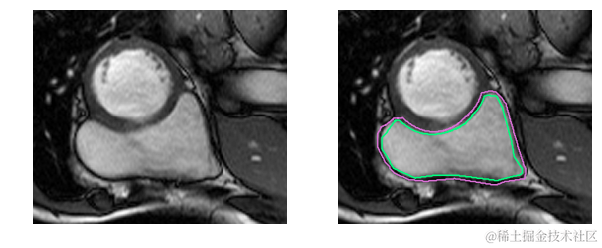

撇开医学术语不谈,要识别RV就更困难了。左心室是一个厚壁圆环,而右心室是一个形状不规则的物体,有薄的壁,有时会与周围的组织混合在一起。这是MRI快照右心室内壁和外壁(心内膜和心外膜)的手工绘制轮廓:

这是一个分割起来很容易的例子。这一个比较困难: